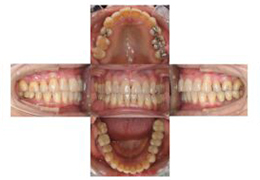

(治療11年後)

67歳、矯正治療後11年経っても状態は非常に安定しています。顎関節、下顎位にアプローチした結果です。

移植歯も問題なく推移していますが、メンテナンスにきちんと通っていただくことが肝要です。